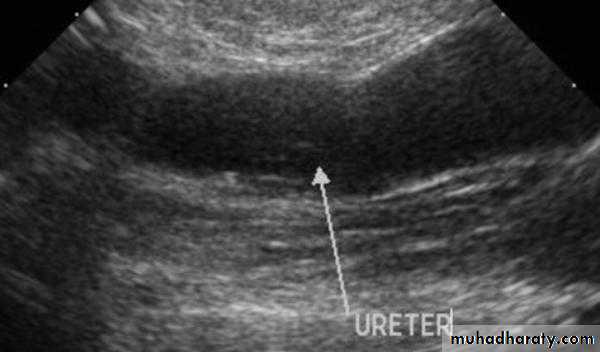

Ureteric hydronephrosis ??

Ureter dilatation in left